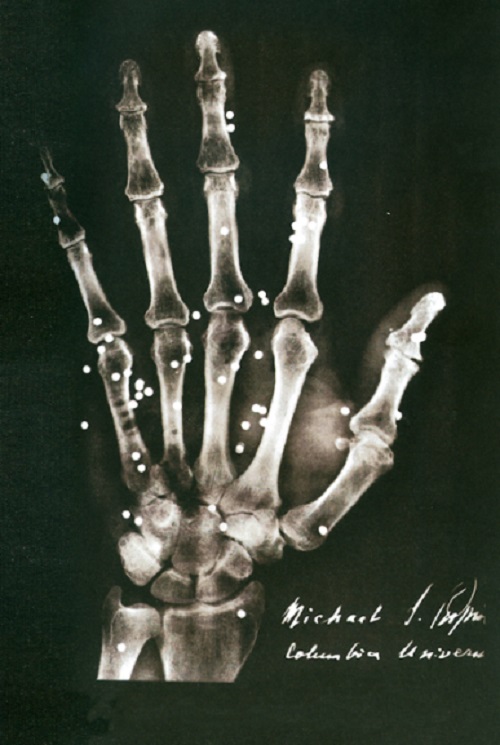

Izložba će predstaviti istorijski razvoj i primenu rendgenske tehnologije u medicini, od otkrića rendgenskih zraka do danas, sa posebnim naglaskom na doprinosima koji su u oblasti rendgenologije ostvarili Nikola Tesla i Mihajlo Pupin. Ciljevi izložbe su i predstavljanje uspeha domaćih preduzeća u razvoju proizvodnje rendgenskih aparata i opreme.

Pored fotografija i dokumenata, na izložbi će moći da se vide i stari rendgenski aparati, oprema i sredstva za ličnu zaštitu od zračenja, prve rendgenske cevi proizvedene u Jugoslaviji, ali i najnoviji digitalni rendgenski uređaji. Sastavni deo izložbe su sadržaji u obliku virtuelne stvarnosti (VR) i edukativne digitalne igre za decu i omladinu koje su kreirali najbolji polaznici besplatnih edukativnih programa za razvoj igara, prijatelja izložbe Nordeus Haba i Krater trening centra. Tokom trajanja izložbe biće organizovana stručna vođenja, predavanja i edukativne radionice za decu, omladinu i studente.